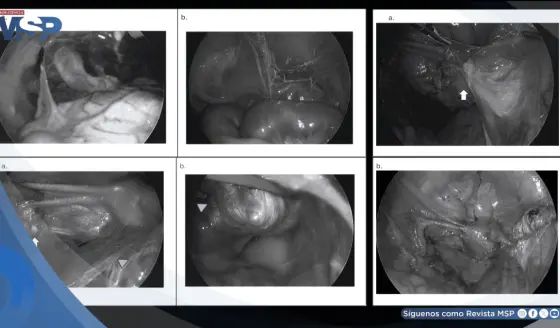

Dolor abdominal severo en paciente de 32 años resultó ser un infarto omental y no apendicitis